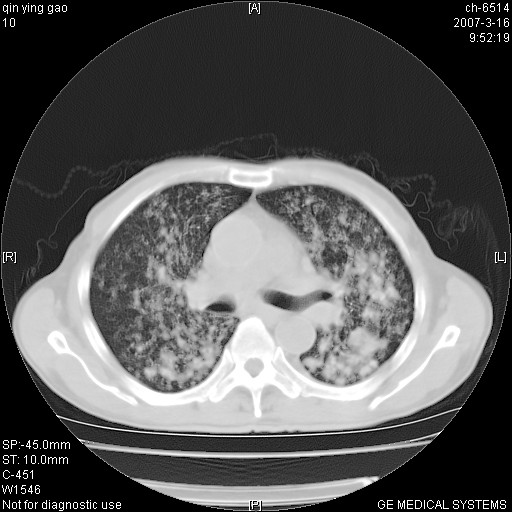

男,64岁.乏力2个月,畏寒、发热1月余。体重下降。血沉加快,白细胞不高。

双肺可见大小不等结节状密度增高影,密度不均,分布不均(双肺上叶为著),亚急性血行播散性肺结核.

(本例特征:以大小不等结节为主,主要分布在双上肺,并部分病灶融合成较大结节,期间搀杂诸多细小结节。从病灶特点与分布形式分析,更趋向于感染。)

中上肺野密布棉团状影,以胸膜下区为界,边缘模糊,可能是小叶或腺泡渗出及实变。全肺野弥漫分布网线样影及细小粟粒样影,可能是细支气管炎及间质内炎症。综合分析应首先考虑气道播散性感染,而肺内多处斑点性钙化,强烈提示陈旧结核复发并支气管播散。建议详细讯问病史